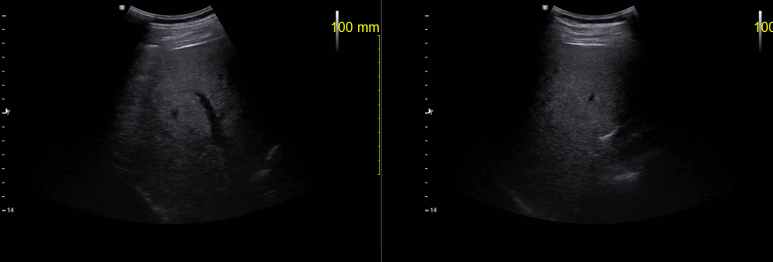

화살표는 십이지장

사각형 아래는 담도가 연결되어 있는 모습

담도가 들어가면 좌우로 분지하고 상부에 다시 갈라지는 모습을 관찰할 수 있다.

당시 지방간 소견과 함께 S5 영역에 저음영 종괴가 의심되었었는데 CT등 이미지로 평가되지 않은 상태